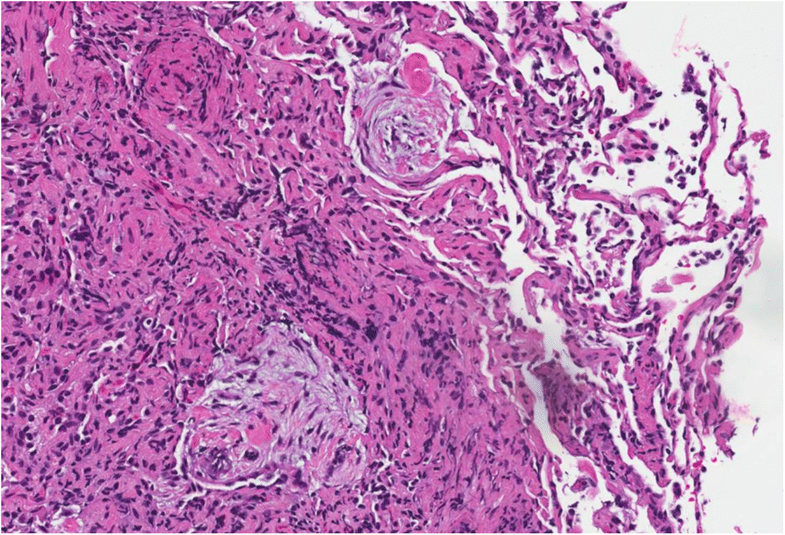

It is also classified under the spectrum of eosinophilic lung disease and as a type of pulmonary angiitis and granulomatosis. In egpa, vasculitis is associated with asthma and eosinophilia. This contraction of the class ii hla repertoire suggests a strong cd4 + t lymphocyte activation, possibly triggered by allergens or antigens.

Eosinophilic granulomatosis with polyangiitis after prolonged intervals of tocilizumab in rheumatoid arthritis Eosinophilic granulomatosis with polyangiitis (egpa) is a rare, but severe systemic vasculitis that can affect skin and other organ systems. Eosinophilic granulomatosis with polyangiitis (egpa), also called churg strauss syndrome, is a rare, chronic disorder and a form of primary systemic autoimmune vasculitis characterized by inflammation of blood vessels.